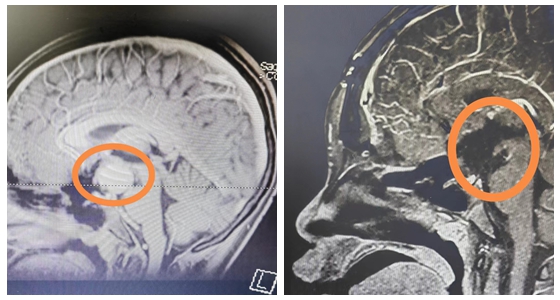

13岁的涵涵身高仅有145cm,体重37kg,比同班的男孩,甚至女孩都要矮小。起初,爸爸妈妈也没有太在意,以为孩子就是“长得晚”。2023年5月份开始,涵涵偶尔会跟爸爸妈妈说自己视物模糊,看不清,这时父母才重视,带涵涵到当地医院就诊。在医生的建议下查了颅脑MRI,问题果然出现在脑袋上,考虑:颅咽管瘤。为寻求手术治疗,涵涵在家长陪同下慕名来到湘雅常德医院神经外科就诊。

据悉,颅咽管瘤是一种先天性的良性肿瘤,多发生于儿童。人在胚胎时期有一种组织叫颅咽管,本该在发育过程中消失,但有少数人,颅咽管残存的细胞没有消失,而是继续缓慢生长,最后形成颅咽管瘤。

颅咽管瘤位于下丘脑和垂体区域,毗邻两大内分泌的中枢,也就是我们说的下丘脑和垂体,上面两侧是脑室,两边是海绵窦,还有颈内动脉,再下面是视神经、视交叉。颅咽管瘤长在脑袋的正中间,周围这么多重要的结构,损伤哪一个都不行,如果损伤了视神经可能引起单侧失明,损伤了视交叉会双侧失明,损伤颈内动脉会带来灾难性的大出血。下面的垂体受到影响,会终生内分泌紊乱,损伤后面的下丘脑不光是带来体温调节障碍,食欲减退,甚至可能导致昏迷。

世界卫生组织称:颅咽管瘤是颅内唯一因为解剖因素而不能治愈的呈恶性结果的良性肿瘤。也就是说,这个良性肿瘤,本该能治好,但因为位置的特殊而极难全切,如果肿瘤不全切,术后极易复发,且对化疗、放疗均不敏感,只能行第二次手术治疗,所以第一次手术能否全切对患者来说至关重要。